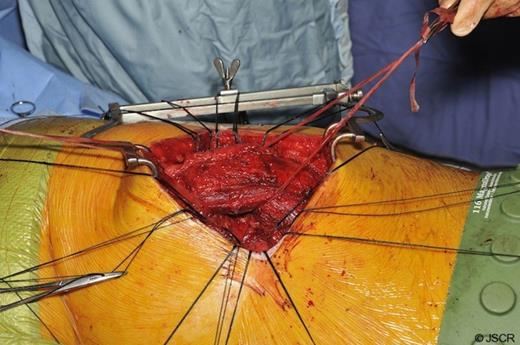

A limited left muscle sparing postero-lateral thoracotomy was used to gain access to the chest. Both the serratus anterior and latissimus dorsi muscles were mobilised and preserved (figure 3). The fractured portions of the seventh and eighth ribs were dissected and subsequently resected. The sixth rib, deemed to be healing appropriately and in-keeping with normal anatomy, was spared.

Next, the site of the lung herniation was identified (figure 4) and interrupted anchoring sutures were lain down (figure 5).

A 15 by 20cm, 1.5mm thick PermacolTM (Covidien, Hampshire, UK) biological implant was used to close the defect (figure 6 and 7). The soft tissues were then reinforced using interrupted sutures. The ribs that had been divided following the excision of the non union fragments were then approximated to restore a more normal intercostal space with interrupted peri-costal sutures. Haemostasis was achieved and a single 28F chest tube was placed within the pleural cavity.

The PermacolTM bioprosthesis (Anterior and Posterior view) Latissimus Dorsi is reflected posteriorly and anteriorly respectively